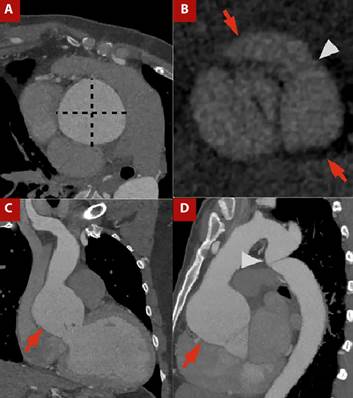

For morphological assessment of the aortic valve using cardiac CT, image acquisition requires cardiac synchronization and a retrospective protocol to capture the entire cardiac cycle, with a field of view (FOV) centered on the heart and aortic root, enabling evaluation of the aortic valve and adjacent structures such as the ascending aorta (Figure 1).

Figure 1 A) Contrast-enhanced CT angiography of the thoracic aorta with cardiac gating, orthogonal plane of the ascending aorta. B) Aortic valve plane in ventricular systole. C) Coronal view and D) Sagittal view.Ascending aortic dilatation is evident, with a maximum diameter of 64 × 64 mm measured in the orthogonal plane (dashed line in A), involving the sinotubular junction (arrows in C and D). A bicuspid aortic valve is present, with fusion of the right and left coronary sinuses (arrows in C) and visualization of the raphe (arrowhead in C). The patient also had thoracicaortic coarctation (arrowhead in D).

Accurate measurement relies on planimetry, which requires alignment of three orthogonal axes through the LVOT to obtain an en face view of the aortic valve and allow assessment of cusp morphology, valve area, and eccentricity index. This is achieved by first identifying the cusp insertion plane in the coronal view and then aligning the orthogonal planes at the same level, generating a cross-sectional view of the valve apparatus (Figure 1A, 1B). 11